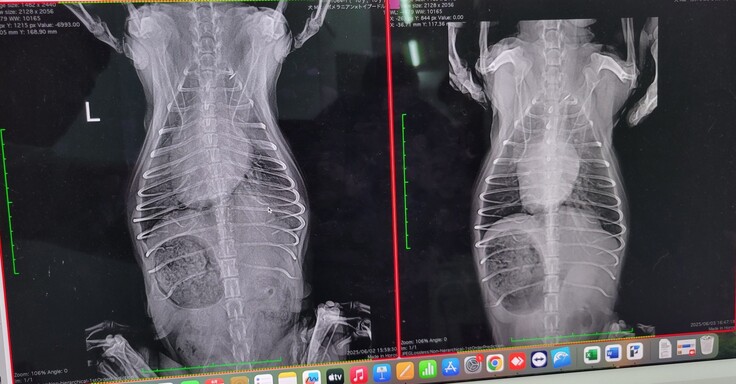

左が入院時・右が一週間後。心臓の周りのもやのようなものが肺水腫とのこと。一週間後には治まり、心臓の大きさも小さくなりました。

その後、失神を起こした後の状況。幸い、この時は肺水腫は再発していないようですが、退院時より心臓が少し大きくなっています。